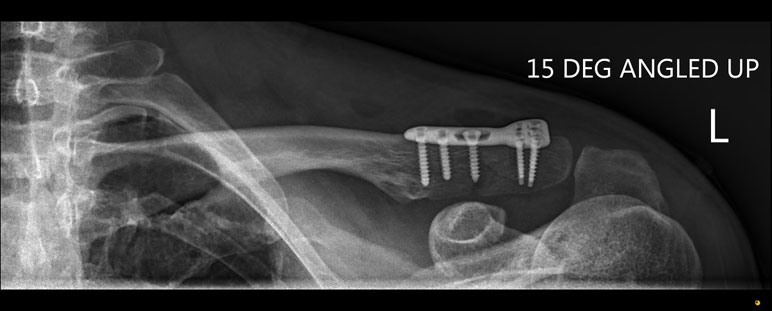

What do clavicle fractures look like on X-ray?

Below are examples of typical fractures that benefit from surgery.

Click an image to enlarge